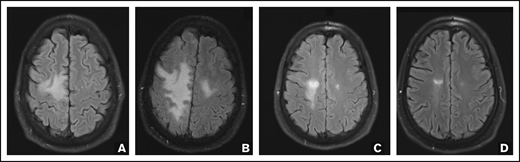

Repeat brain MRI after 2 N-803 cycles on 16 October 2017 showed a worsening extent of the FLAIR abnormality (Figure 1). However, the patient’s strength was improving, and treatment was continued. Subsequent brain MRIs demonstrated marked improvement in the T2/FLAIR white matter lesions, and the most recent brain MRI, 759 days after initiation of N-803, continued to demonstrate response. Qualitative CSF JCV PCR has remained undetected since December 2017. CSF specimens were sent to the National Institutes of Health (NIH) for ultrasensitive quantitative JCV PCR, and the DNA copy number decreased from 31 copies/mL in December 2017 to 16 copies/mL in February 2018 and 11 copies/mL in April 2018. Identification of the JCV DNA variant as prototype was performed at the NIH using the Multiplex qPCR assay. N-803 was stopped after 8 total cycles, and the patient continues to take mefloquine and mirtazapine. His neurologic deficits continue to improve, and he is now able to ambulate with a cane. His last follow-up examination was April 2020 (+926 days after initiation of N-803 therapy), and he remains stable with slow and steady neurologic improvement and no evidence of graft-versus-host disease or acute myeloid leukemia.

FLAIR MRI images. Axial FLAIR MRI images were obtained before initiation of N-803 (A), after 2 cycles (B) and 8 cycles (C) of N-803, and 759 days after initiation of N-803 (D), demonstrating improvement in the posterior right frontal subcortical white matter lesion.